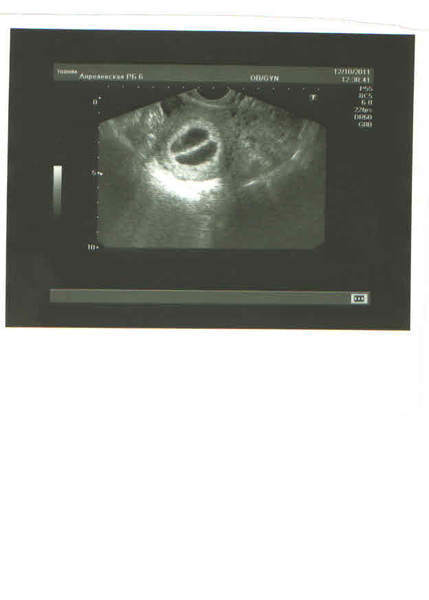

Было 6-7 недель. Даже снимок дали. Я не спец, но кажется здесь четко видны 2 ПЯ.

Не Тонь мне кажется энто одно плодное яйцо разделенное перегородкой)))))))))))))))) У меня диамниотическая монохориальная двойня. Т.е. близнецы ,т.е. одна плацента на двоих, но разные мешки. были. т.е их разделяла моих перегородка, А там фиг знает может энто и 2 ПЯ)))) НО вот прям судя как они похожи четко, то прям близнецы))) твои девчушки похожи даже больше чем мои 100% близнецы))))))))))а в принципе какая на фиг разницы . Самое главное здоровые

вот здесь четко видно 2 отдельных ПЯ. срок 6 недель.

дихориальная диамниотическая